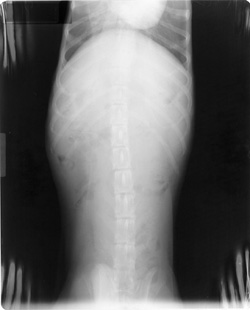

Stuck in Processor

See grid lines.